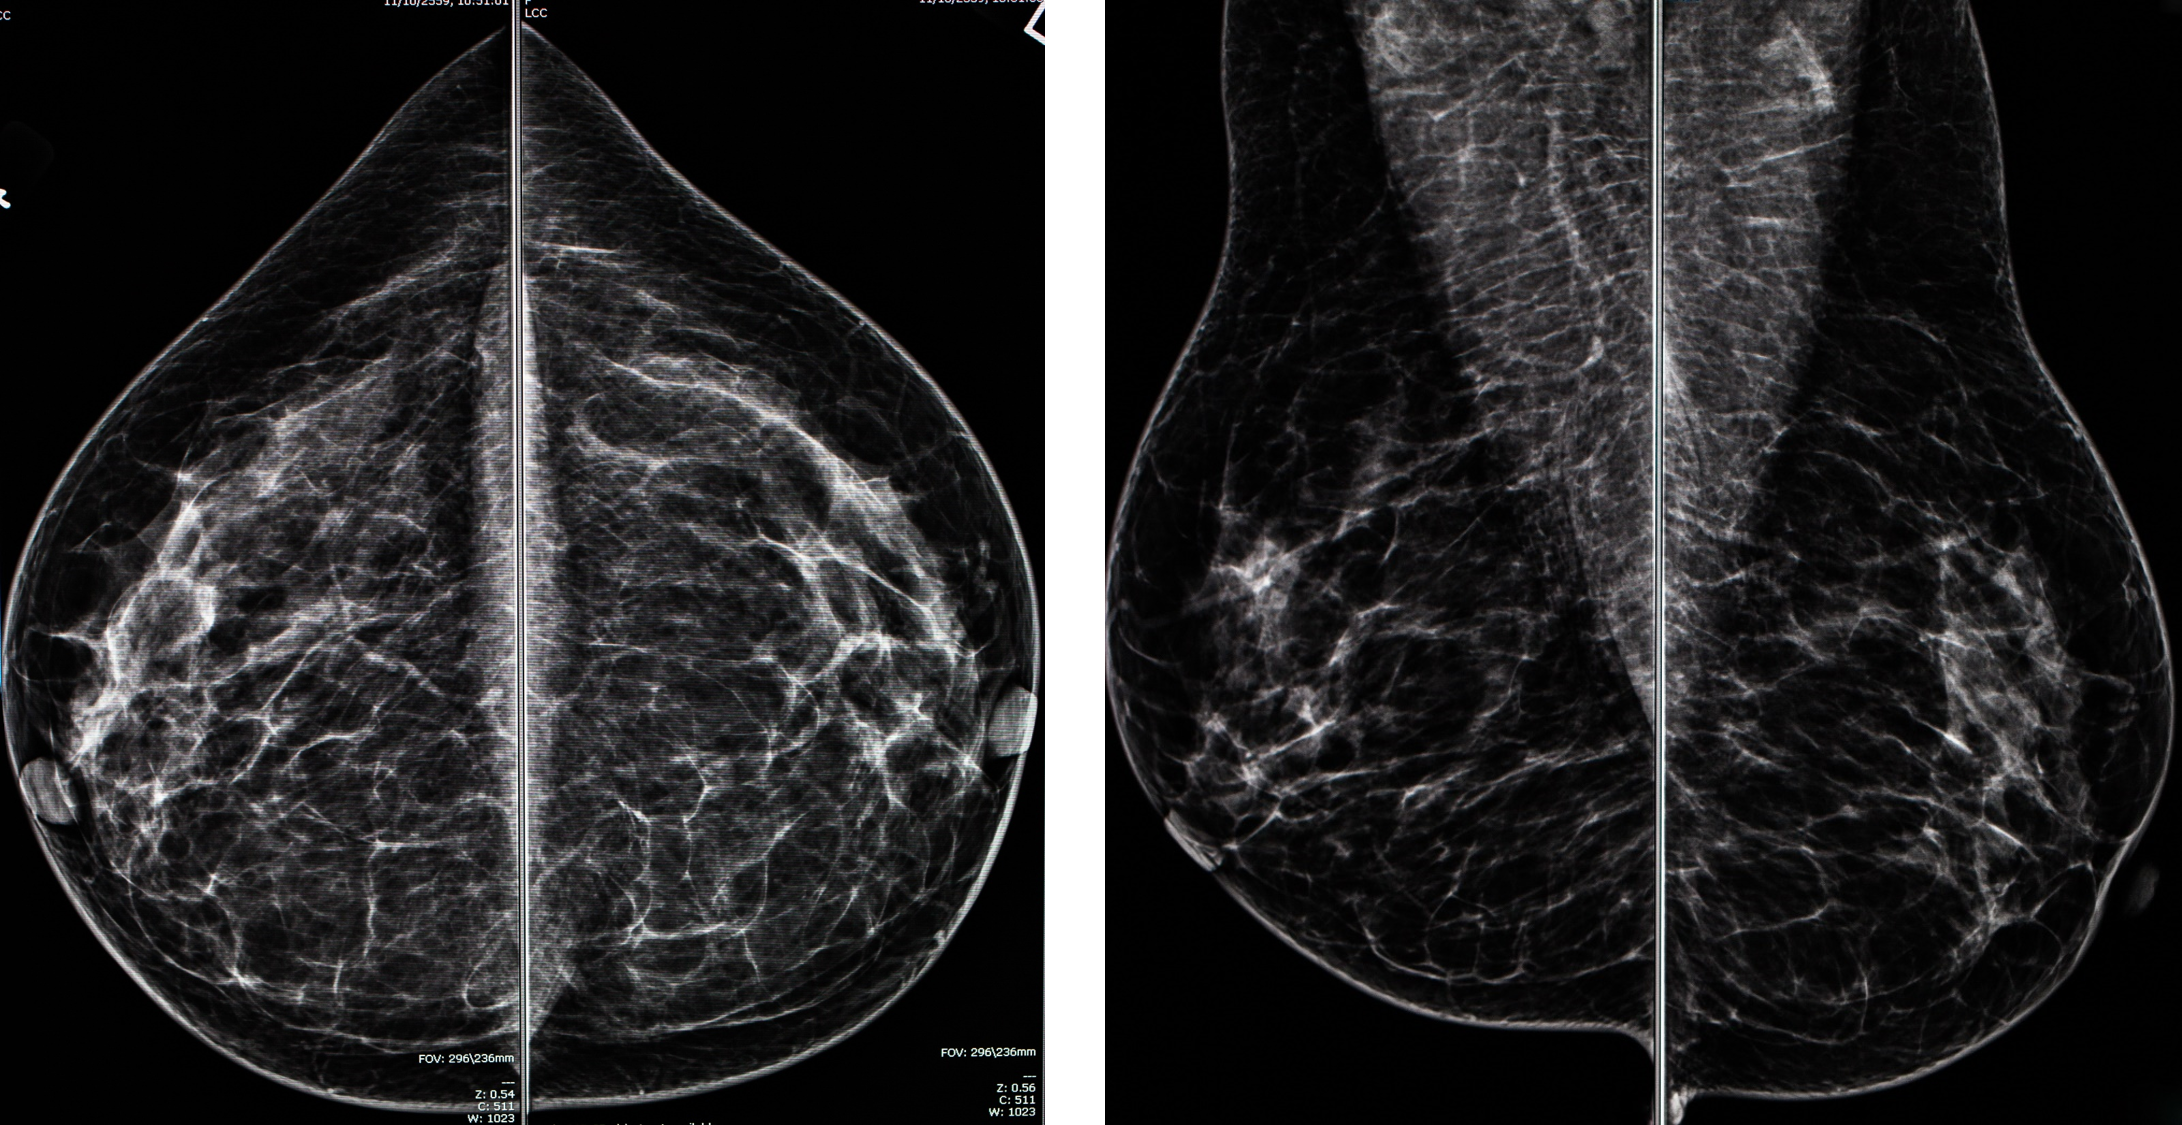

이것이 일반적인 유방촬영술의 결과물입니다. 어느 병원에서 찍든 두가지 방법의 이미지를 얻고, 방향은 정해져 있습니다. 각각 알아볼까요?

이 이미지는 오른쪽(R), 왼쪽(L) CC(craniocaudal) view입니다. 쉽게 말해 유방을 위아래로 눌러 찍은 영상입니다. 이 영상에서는 내측 유방이 잘 포함되어야 하고 외측도 최대한 포함 되게 찍습니다. 영상의 위가 유방의 바깥쪽, 아래가 유방의 안쪽입니다.

이 이미지는 오른쪽(R), 왼쪽(L) MLO(mediolateral oblique) view 입니다. 이는 유방을 안쪽 바깥쪽으로 압력을 주는데, 약간 비스듬히 압박 하는 방법입니다. 이 방법은 단일 촬영으로 가장 많은 유방조직을 보여줄 수 있습니다. 영상의 위가 유방의 위쪽, 아래가 유방의 아래쪽 입니다.